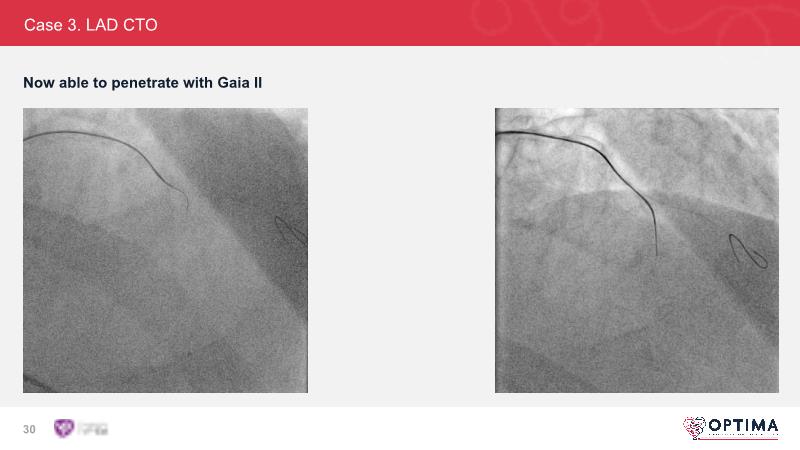

Cracking calcium: intravascular lithotripsy’s unique mode of action in treating calcified lesions – What's the evidence?

Watch this GulfPCR-GIM 2022 session to understand the unique mechanism of action of IVL, the use of intravascular imaging in calcium identification, the gender gap, disrupted CAD trials, and the evolution of treatment of calcified lesions together with the role of IVL.